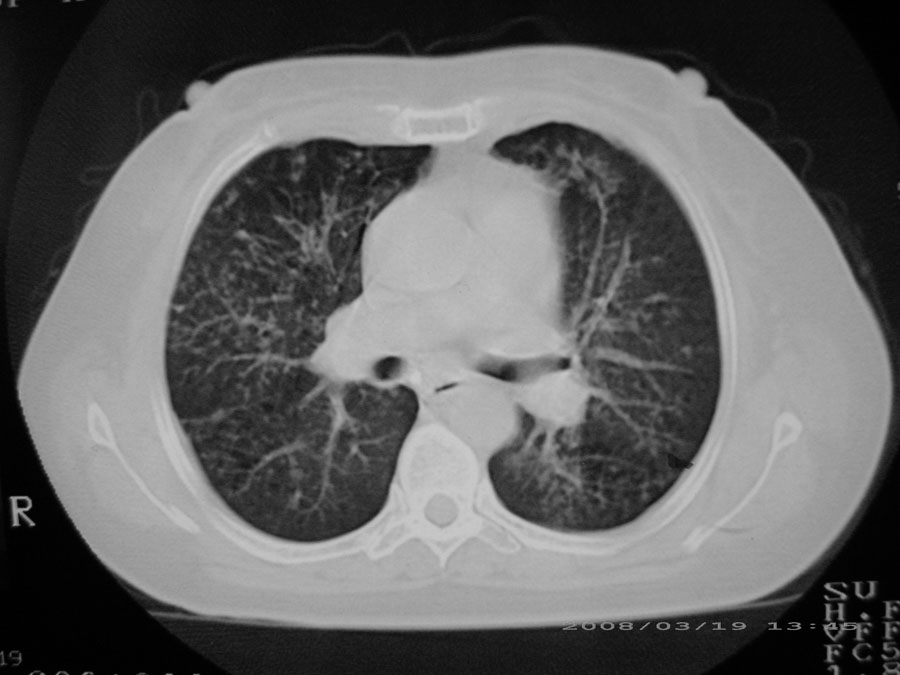

粟粒性结核

本病例主要是癌性淋巴管炎与结节病的鉴别。好好查查吧。

密漫性沿纹理走行小结节影;有间质纤维化;可考虑尘肺;以图而论

血行播散性肺结核

双肺网状结构,小叶间质结节状增厚,考虑结节病

综合大家意见,结核、结节病、肺泡细胞癌均有可能,间质性肺炎暂不考虑,病灶纠集不明显,纵隔未见钙化淋巴结,尘肺可能性不大,但还是要密切结合临床诊断。

今天重新仔细看了看,矽肺确实不能除外,病灶主要表现为间质结节及纤维化。好好问问病史吧。